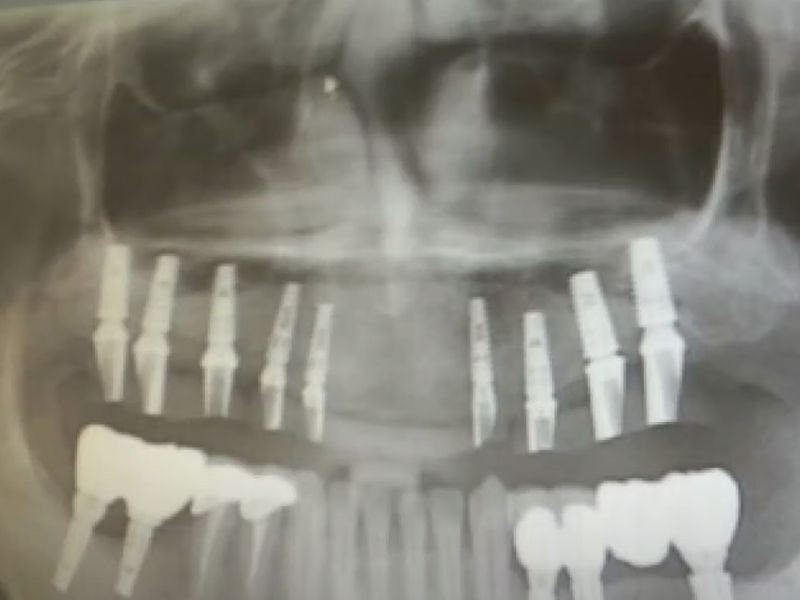

韓國濟州島發生一起牙科手術致死事件,死者為一名61歲的中國男子。根據韓國 KBS 新聞 6 月 13 日的報導,該名男子於今年早些時候在濟州島進行種植牙手術後不幸身亡,目前警方正在調查此案。

死者的家屬表示,事件發生在 2 月 28 日,死者在濟州島一家牙科診所接受了種植牙手術。手術結束後,死者感到劇痛,並在當晚不幸去世。根據法醫的屍檢結果顯示,死因為下頜骨粉碎性骨折引起的出血。

接到報警後,濟州警方立即展開調查,認為這可能是業務過失致死案件。警方對涉事牙科診所進行了扣押搜查,以查明該診所是否存在過失行為。

對於此事,涉事牙科診所表示,死者在手術後並無異常,當天便自行回家。診所表示,如果確認有責任,將會承擔相應的責任。